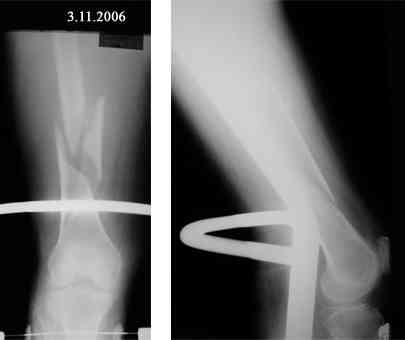

Продолжая тему "оскольчатый перелом бедра"

В продолжение темы оскольчатого перелома бедренной кости.

Р-граммы в динамике